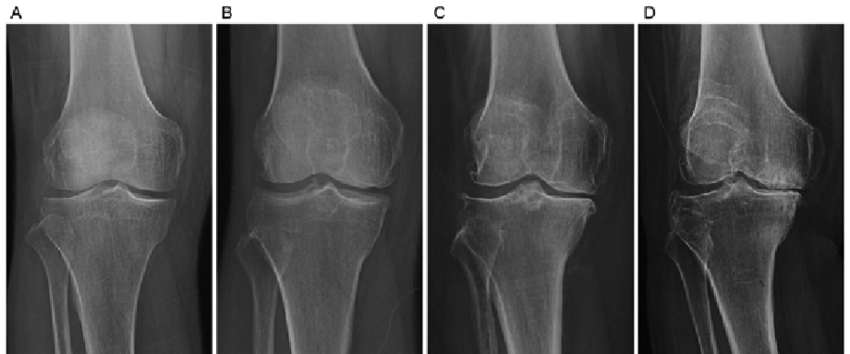

Graus de Artrose (Kellgren–Lawrence)

- Grau 1: Sinais discretos

- Grau 2: Estreitamento leve

- Grau 3: Desgaste moderado

- Grau 4: “Osso com osso” (desgaste avançado)

Diagnóstico da Artrose

O diagnóstico é feito por exame físico e radiografia. Em alguns casos, ultrassom e ressonância ajudam a avaliar estruturas adicionais, como derrame articular e tendões inflamados.